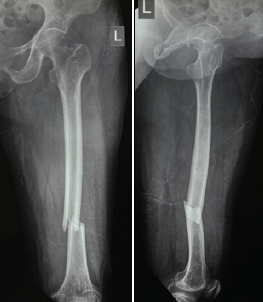

Figure 1: Pre-operative anteroposterior and lateral views showing a distal third fracture of femur.

Out of all study participants, 58 patients had closed fractures and rest 2 patients had compound fractures. The mean operation-injury interval was 5.5 ± 0.67 days for antegrade nailing and 5.8 ± 0.65 days for retrograde nailing. The mean duration of the surgery was 85 ± 2.15 min for retrograde nailing and 95 ± 1.39 min for antegrade nailing. Mean time for radiological union with retrograde nailing was 10 ± 0.38 weeks (Fig. 1, 2, 3, 4) and with antegrade nailing, it was 14 0.44 weeks (Fig. 5, 6).